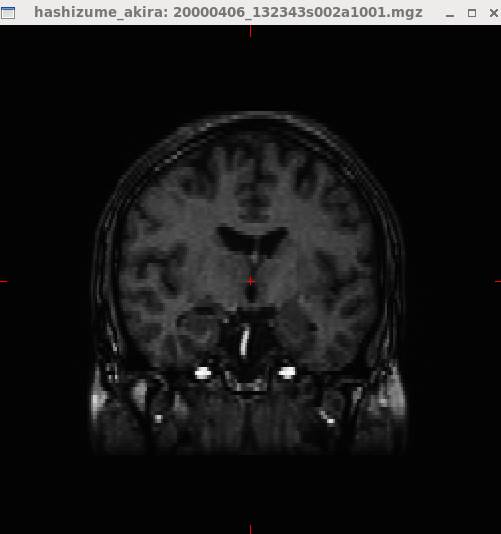

mri_convert

20000406_132343s002a1001.nii.gz 20000406_132343s002a1001.mgz

freeviewで開いたところです。